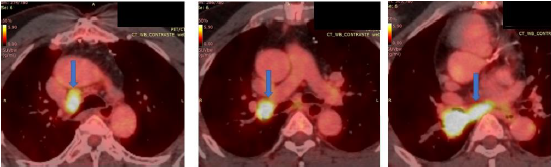

Idoso de 62 anos, com antecedentes de neoplasia de orofaringe (carcinoma de células escamosas), em 2015, tratado com radioterapia, realizou transplante hepático, em 2019, por cirrose hepática por vírus C e vem em acompanhamento de doença coronariana. Relata ser ex-tabagista há 20 anos, carga tabágica 20 maços/ano. A tomografia computadorizada de tórax demonstrou imagem compatível com lesão expansiva, medindo 38x31mm, no lobo inferior direito (LID), com obliteração do brônquio lobar correspondente. Realizou videobroncoscopia que evidenciou lesão exofítica, ocluindo o brônquio do LID. A biopsia da lesão confirmou o diagnóstico de carcinoma de células escamosas. Foi realizado PET-CT para estadiamento da neoplasia (imagem abaixo), com formação expansiva no LID com SUV máximo de 13,6 e linfonodos e linfonodomegalias nas cadeias paratraqueal inferior direita, paratraqueal inferior esquerda, hilo pulmonar direito e subcarinal, com SUV máximo de 9,6 no hilo direito, que mede 22x19mm.